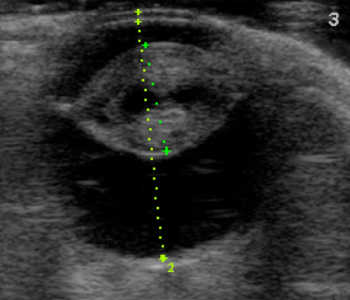

【超音波(エコー)検査】

目の中、特に硝子体や網膜など水晶体の裏側がどのような状態なのか調べます。エコー検査により、白内障の混濁状態や網膜剥離や眼内出血などの合併症の評価を行います。

犬 網膜剥離

網膜剥離